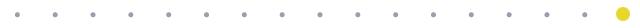

经过B超检查发现,龚女士的 子宫内有两个胚胎,子宫外输卵管的部位,还有两个胚胎。

龚女士B超检查单——

红色箭头处便是跑到宫外的“两个淘气宝宝”